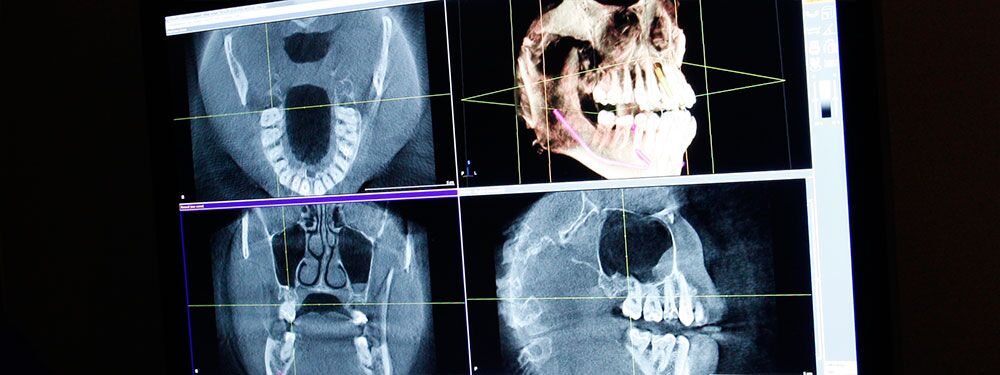

DVT 3D Röntgen­diagnostik

Die Digitale Volumentomographie (DVT) ist eine Weiterentwicklung der Computertomographie. Ähnlich wie beim Computer-Tomogramm (CT) werden bei der digitalen Volumentomographie ( DVT ) Körperbereiche dreidimensional abgebildet. Seit 1999 haben wir auf dem Gebiet der DVT- Untersuchung und Auswertung geforscht, veröffentlicht und Vortragspreise gewonnen.

Während beim CT die untersuchte Region in einzelnen dünnen Schichten gescannt wird, die aneinandergesetzt werden, erfasst die DVT innerhalb weniger Sekunden die gesamte Untersuchungsregion in einem einzigen Umlauf. Daraus resultiert eine um ca. 75-80 Prozent verminderte Strahlendosis bei vergleichbarer Bildqualität. Gleichzeitig treten beim DVT im Gegensatz zum CT kaum Metallartefakte auf, was gerade bei der Darstellung und Diagnostik von Zähnen mit metallischem Zahnersatz oder kieferorthopädischen Brackets der Fall ist.

So können dreidimensionale Bilder des kompletten Gesichtsschädels in kurzer Zeit, ohne Metallartefakte bei gleichzeitig geringer Strahlenbelastung erzeugt werden. Da der Patient nur für wenige Minuten in einem offenen Gerät steht, eignet sich diese Darstellungsmethode für alle Altersklassen!

Durch die dreidimensionale, plastische Darstellung der Gesichtsanatomie inklusive der Kieferhöhlen und des Kauapparats, können außerdem wichtige diagnostische Informationen vor kieferchirurgischen Eingriffen, zur Planung von Implantaten oder kieferorthopädischen Maßnahmen gewonnen werden.